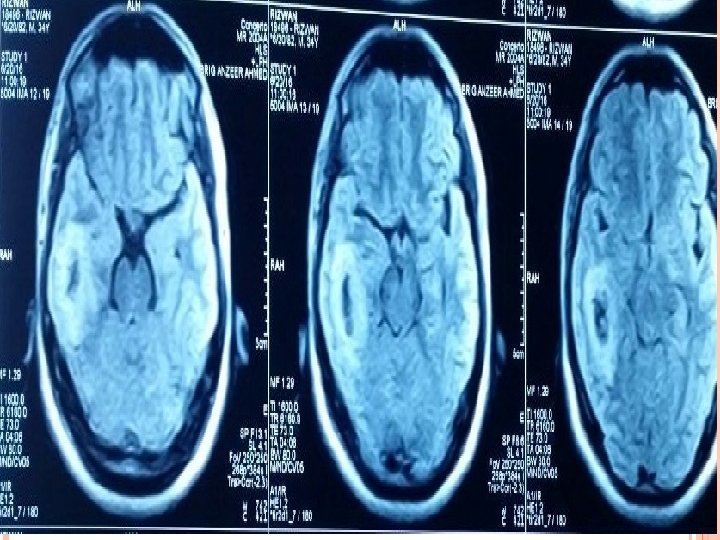

DEMOGRAPHIC DETAILS Name : Father name : Age/Sex : R/O : Occupation : D. O. A : M. O. A : Rizwan Saeed Mohd Saeed 34 years/ M Rawalpindi Employee in oil and gas company 19 -6 -16 Emergency

INVESTIGATIONS Blood Tests CBC (TLC-12000/u. L) CRP (3. 2 mg/L) ESR (28 mm/hr). Imaging CT scan Brain ( plain ) CT scan Brain with contrast. MRI Brain with contrast.

MRI T 1 : necrotic center ( hypointense) Capsule ( hyperintense) Edema ( hypointense) T 2 : necrotic center ( hyperintense) Capsule ( hypointense) Edema ( hyperintense)